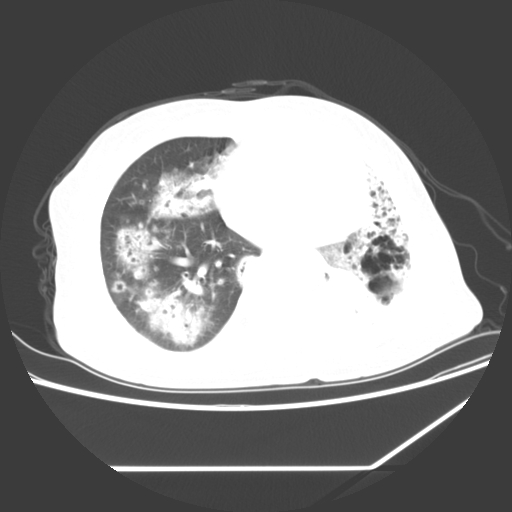

标题: CT25393:病人45岁,咳嗽,吐黄痰带血丝,发热,胸闷月余

1、左肺中央型肺癌并双肺弥漫性转移   2、双肺部感染    3、肺大泡     4、左侧胸腔积液

双侧肺弥漫性病变,可见“空泡征”及“蜂窝征”,考虑肺泡癌可能性大,左侧胸腔积液,考虑胸膜受累可能!

1)不排除肺泡癌可能。2)左侧胸腔积液。